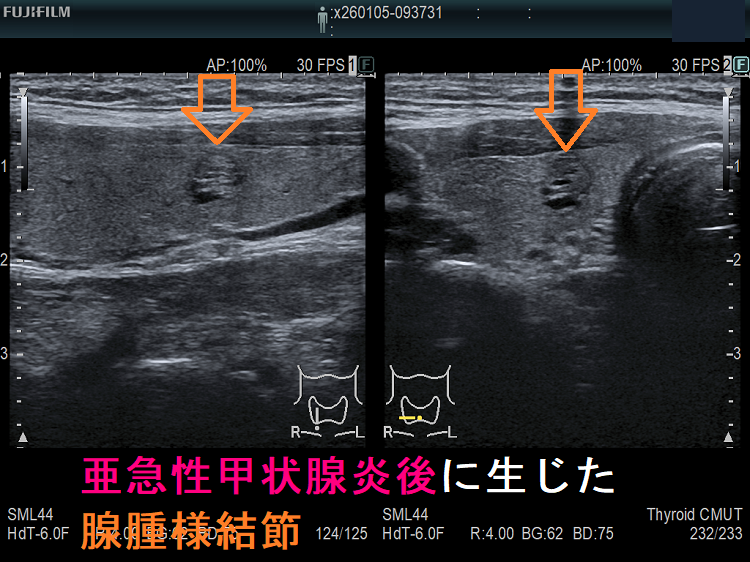

亜急性甲状腺炎治癒後;矢印が腺腫様結節

上記のようにならなくても、亜急性甲状腺炎で甲状腺組織が破壊され、さらに代償的の組織増殖が起こると、

- のう胞変性(嚢胞変性);甲状腺組織が溶けてしまい、空洞ができる

- 代償的に組織が増殖し、腺腫様結節(過形成結節)→腺腫様甲状腺腫

が生じます。長崎甲状腺クリニック(大阪)では、亜急性甲状腺炎が終息して数カ月後に、さらには年単位で甲状腺超音波(エコー)検査を施行しています。